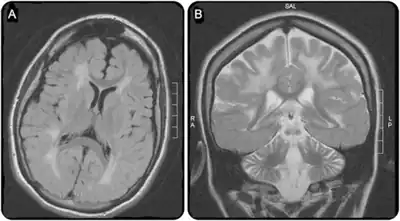

a)Extensive white matter disease b) atrophy of frontal hemispheres and cerebellum -